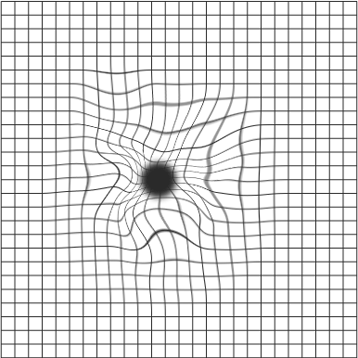

Bei der epiretinalen Gliose bilden sich Membranen auf der Netzhaut, die erhebliche Zugkräfte auf die Netzhaut ausüben können. Es zeigen sich Netzhautschwellungen und Falten, die der Patient als Verzerrungen im Bild wahrnimmt. Die Angaben über die Häufigkeit der Veränderung liegen bei den 70 bis 80 jährigen zwischen 2-20%. Die Ursache lässt sich nicht immer klären, bekannt ist das häufigere Auftreten nach Netzhautlöcher in den Außenbereichen der Netzhaut, auch nach Laser- oder Kältebehandlungen der Netzhaut, nach Entzündungen, bei unterschiedlichen Gefäßerkrankungen der Netzhaut oder nach stumpfen Verletzungen des Augapfels.

Risikopatienten empfehlen wir 1x wöchentlich mit jedem Auge einzeln diesen Test durchzuführen. Entsprechene Testkarten können Sie bei Ihrem Augenarzt erhalten.

Therapeutisch kommt nur eine operative Entfernung der Membranen in Frage. Dies wird in der Augenklinik Nord-Heidberg mittels minimal invasiver 23 G- oder 25 G-Technik durchgeführt, bei der nur 3 kleine Öffnungen mit 0,6 bzw. 0,5 mm Durchmesser an der Außenseite des Auges angelegt werden müssen. Diese minimalinvasive Technik ermöglicht eine kurze Operationszeit, kurze stationäre Verweildauer und schnelle Rehabilitation des Patienten.

Das Verzerrtsehen wird häufig schon nach wenigen Wochen besser, die Erholung der Sehschärfe kann hingegen bis zu einem Jahr dauern.